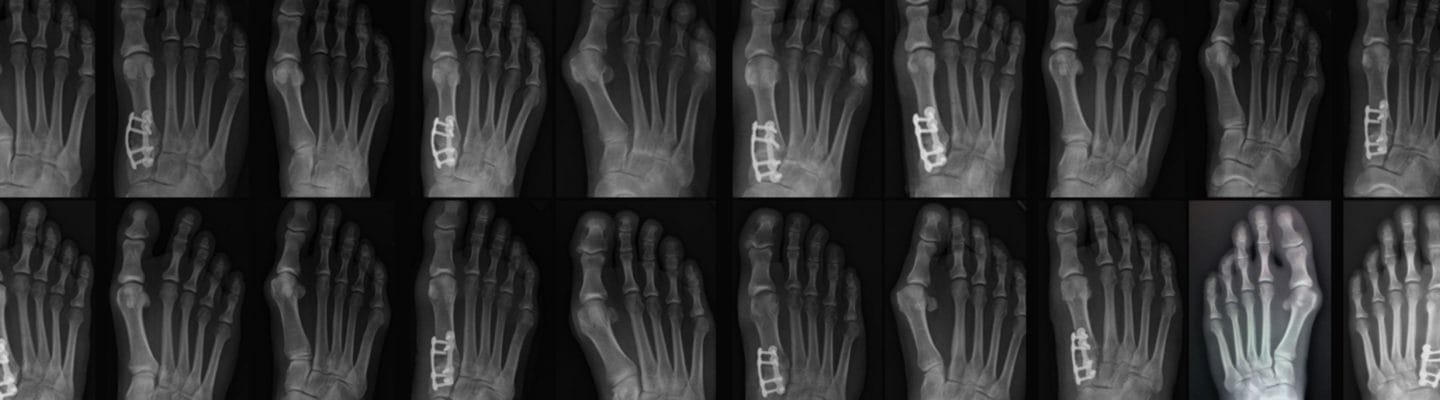

Clinical Case Examples

Before and Afters

Individual results may vary. These results are specific to these patients only. All constructs shown are at the surgeons’ discretion.